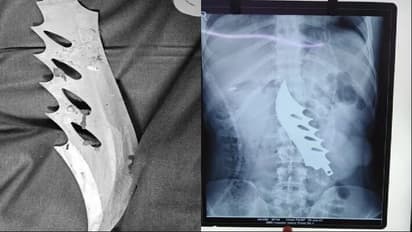

जयपुर, 25 जून. राजस्थान की राजधानी जयपुर के एसएमएस अस्पताल में रविवार दोपहर में एक बड़ी सर्जरी की गई है। पेट के अंदर फंसा हुआ 8 इंच लंबा खंजर 7 डॉक्टरों की टीम ने निकाला है। करीब 3 से 4 घंटे चले ऑपरेशन के दौरान मरीज का काफी खून बहा, लेकिन बाद में उसे बचा लिया गया। फिलहाल वह 2 दिन तक डॉक्टर से ऑब्जर्वेशन में है। उसके शरीर में आंते, पेनक्रियाज और यहां तक की रीड की हड्डी को भी मामूली चोट लगी है। पूरा विवाद शराब पीने की बात को लेकर हुआ था।

इस पूरे मामले में चाकसू थाना पुलिस ने केस दर्ज कर लिया है। पुलिस ने बताया कि टोंक निवासी आकाश मीणा और उसके कुछ साथी कल देर रात चाकसू थाना इलाके में हाईवे पर स्थित एक ढाबे पर खाना खा रहे थे। इसी दौरान एक शराबी वहां आया और उसने आकाश और उसके दोस्तों से विवाद कर लिया। आकाश और उसके दोस्तों ने शराबी की पिटाई कर दी और उसे वहां से भगा दिया, लेकिन जाते-जाते उसने आकाश के पेट में खंजर घोंप दिया। वह उसे बाहर निकालता इससे पहले खंजर का हत्था टूट गया और खंजर पेट में ही फंसा रह गया।

रविवार सवेरे करीब 10:00 बजे उसकी सर्जरी की गई जो दोपहर करीब 1:00 बजे तक चली। इस दौरान सर्जरी विभाग के डॉक्टर नरेश, दिनेश, रितेश, डॉक्टर आशिमा समेत स्टाफ मौजूद रहा। सभी ने मिलकर इस सर्जरी को सफल बनाया। डॉक्टर्स का कहना था की खंजर के कारण पेनक्रियाज, बड़ी आंत और शरीर के अंदरूनी अंगों को नुकसान पहुंचा है , डैमेज बहुत ज्यादा है , रिकवर होने में काफी समय लगने वाला है।